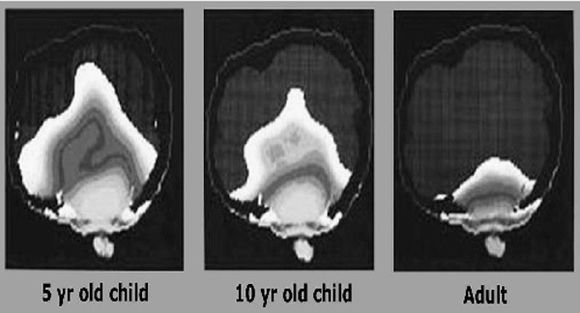

Studien konkluderer med at det er omtrent dobbelt så stor risiko for å utvikle hjernesvulst i de mest utsatte områdene i hjernen ved langvarig bruk.

– Telekombransjefinansierte studier har rapportert sterkt tvilsomme resultater sammenlignet med uavhengige studier. De svenske studiene, uavhengig av industrifinansiering, har rapportert om risiko for hjernesvulster fra bruk av mobiltelefon og trådløs telefon. Resultatene indikerer at mobiltelefonbruk i 10 år omtrent dobler risikoen for å få diagnostisert en svulst på samme side av hodet som mobiltelefonen holdes, skriver forskerne i sin konklusjon.

– Derfor er det tilrådelig å redusere mobilbruken til veldig få og korte samtaler. Mennesker under 20 år bør kun ha mobiltelefoner som tillater SMS, ettersom risikoen er langt høyere hos unge mennesker, skriver forskerne.

Videre mener de at det gjentatte ganger har blitt bevist at strålingen fra basestasjoner er skadelig for helsen, og at dagens strålingsgrenser er basert på et falskt premiss om at det kun er oppvarmingseffekter på kroppen som er skadelige.